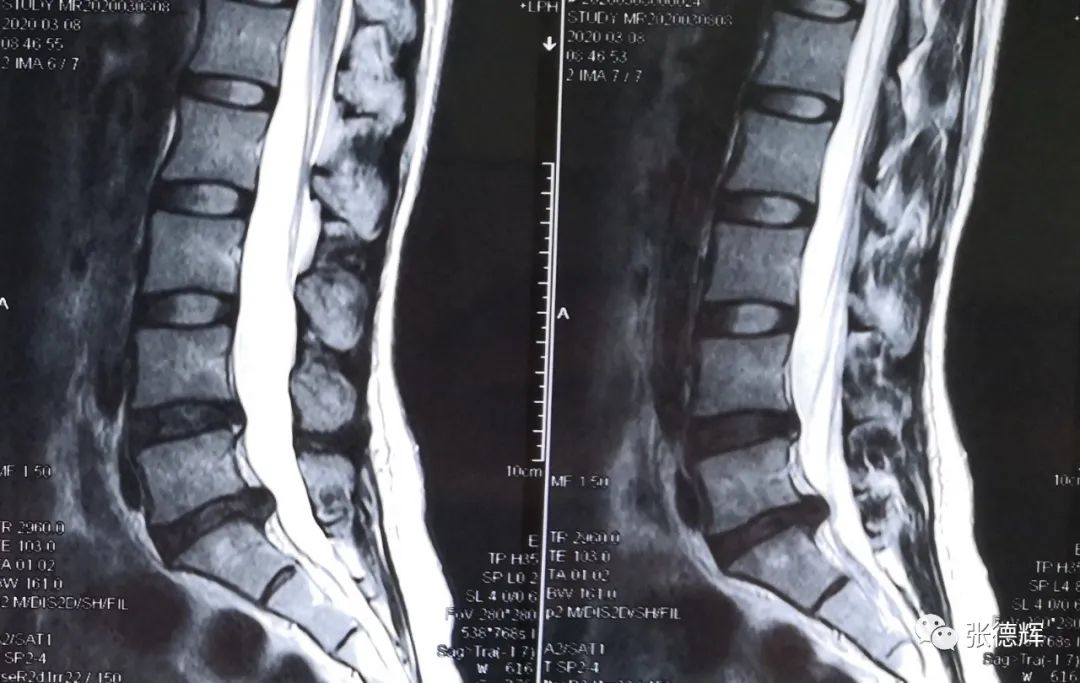

影像检查提示:腰5-骶1椎间盘左后突出,神经根受压(腋下型突出)

腰椎核磁共振检查,矢状位片提示腰5-骶1椎间盘突出,横断位片可见突出物位于神经根腋下